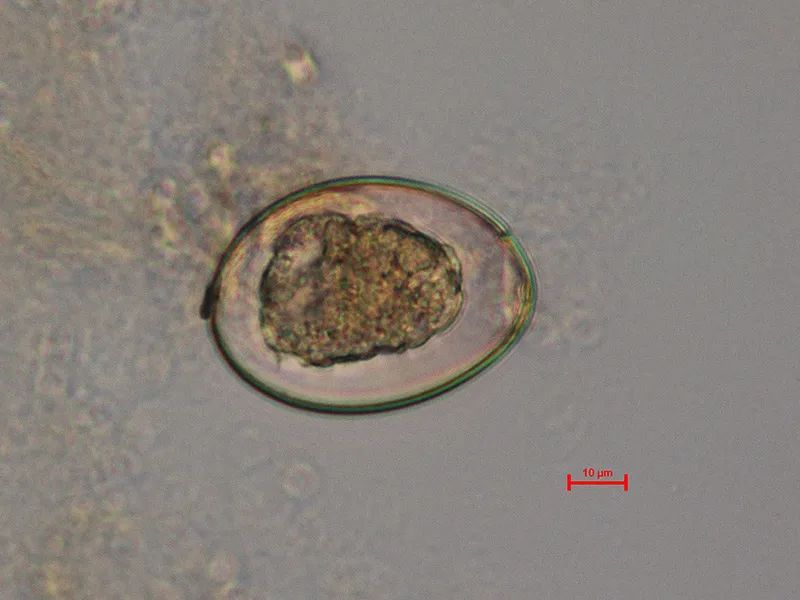

缩小膜壳绦虫卵(40x)六钩蚴

▼「长膜壳绦虫卵」形态特征:类圆形,大小约(60-79)×86 um.

▼「短膜壳绦虫卵」形态特征:圆形或椭圆形,大小为(48-60)×(36-48)um